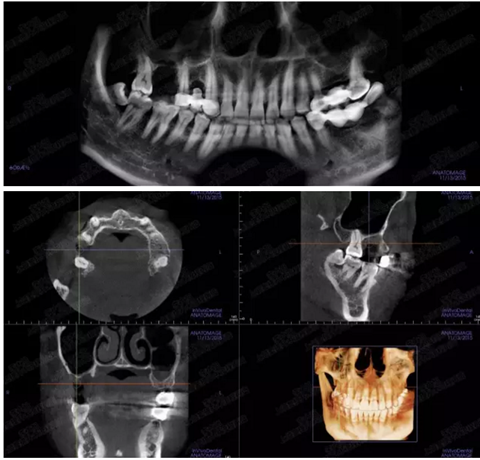

病例二

剩余骨量2mm

003.png

提升10mm

004.png

病例三

剩余骨量3mm

005.png

006.png

病例四

剩余骨量2mm-5mm且存在斜形竇底

007.png

提升8mm

008.png

009.png